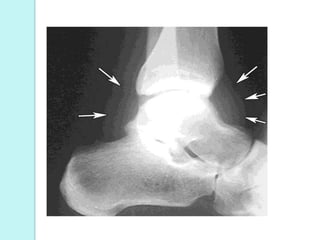

Radiography

 Early:

◦ Soft tissue swelling Joint space widening

 Late (2-3 w):

◦ Erosion

◦ Joint space narrowing